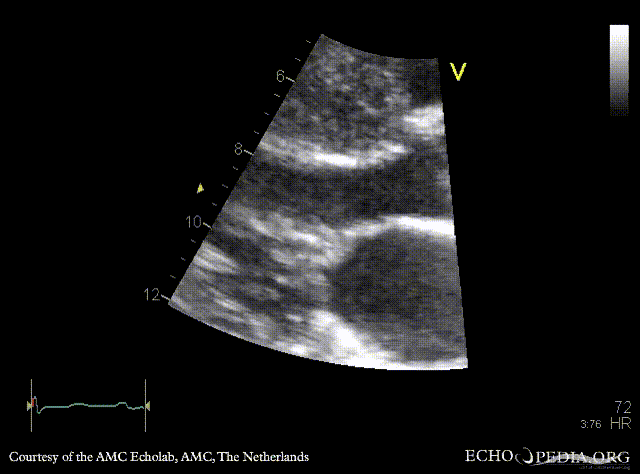

PLAX: severe concentric hypertrophy of left ventricle, SAM of AMVL PLAX zoom: SAM of AMVL